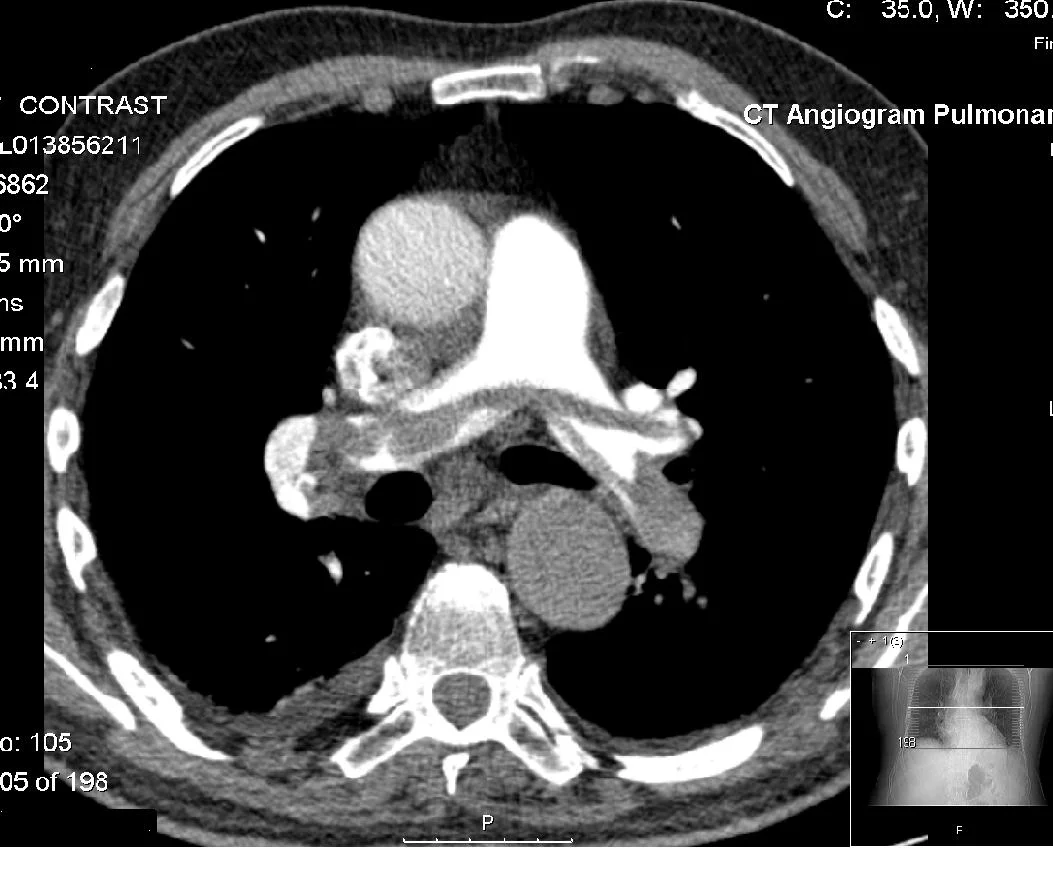

Computed tomography (CT) is a commonly used imaging modality in the US. In 2013, greater than 74 million CT scans were ordered. Although recently there has been a decrease in the need for contrast for certain diagnostic needs, contrast remains very important in the diagnosis of pulmonary embolus, aortic pathology, infectious processes, and other soft-tissue pathology. Acute kidney injury (AKI) has been a concern for many years and the teaching has been that contrast can increase the risk of acute kidney injury. Recent literature has addressed this issue and this month’s journal club offers a synopsis of these articles.